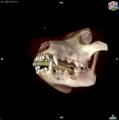

CT - angiografie (kočka)

CT - lebka